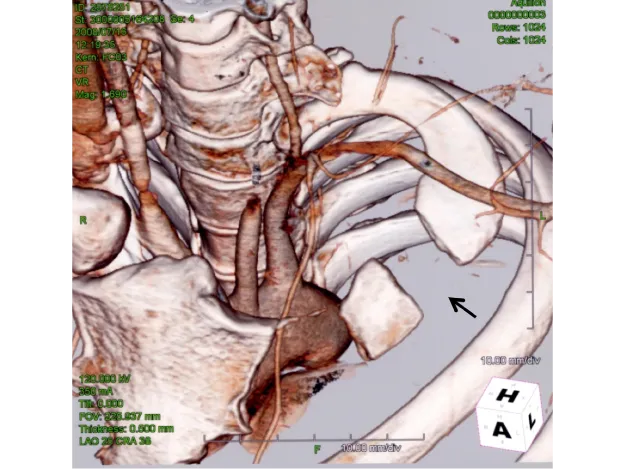

このうち①は国際的に標準的な手術で、腋窩到達法と鎖骨上到達法があります。重要な点は、第一肋骨後方を肋横突関節まで確実に切除することです〈図11 a,b〉。

図11

図11. 適切な第一肋骨切除法

• 【切除された左第一肋骨】図の追加部分まで切除され上端は椎体横突起との関節(矢印)

• 術後のX線撮影で、関節(矢印)まで切除されていることが確認される。